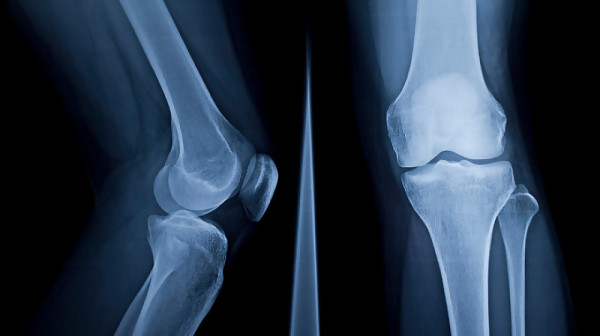

Изследователи от Университета в Съри съобщиха, че разработена от тях технология използва машинно обучение, за да визуализира как ще изглежда коляното след една година и да оцени риска от заболяване.